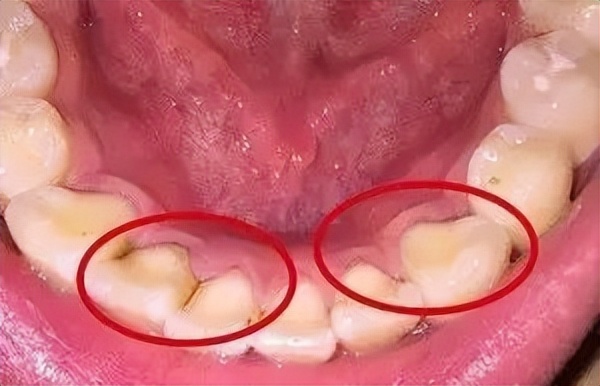

有些附着在牙龈下面,有些会在大牙(磨牙)上面的沟沟里。

1、 牙结石:牙结石有黄色或者黑色,但是不管黑和黄,它都是一种不好的东西。是由于口腔环境长期不佳,细菌和色素沉积之后,附着在牙齿上,有些在牙齿根部与牙龈相连处,有些在大牙(磨牙)上面的沟沟里

2、 龋齿(蛀牙):当牙齿发生龋坏之后,牙齿的表面会被腐蚀,发展到一定程度,会形成黑色的龋洞(蛀洞),而这个时候,必须马上治疗。